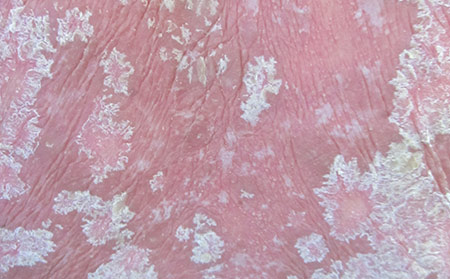

斑塊狀牛皮膚癬

這是最常見的一種。10個牛皮膚癬患者中大約有8個患有這種病。你可能會從醫生哪里聽到尋常型牛皮膚癬。

癥狀:斑塊狀牛皮膚癬會導致皮膚凸起,發紅,被銀白色鱗片覆蓋。這些斑塊可能會癢和疼痛。它可以出現在身體的任何地方,但經常出現在以下部位:肘部、膝蓋、頭皮、腰部